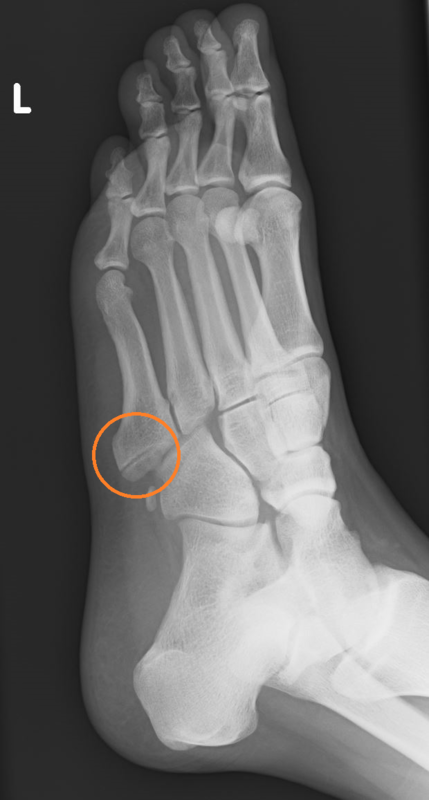

画像検査(レントゲン)

赤く囲んだ部分が骨折している部分です。